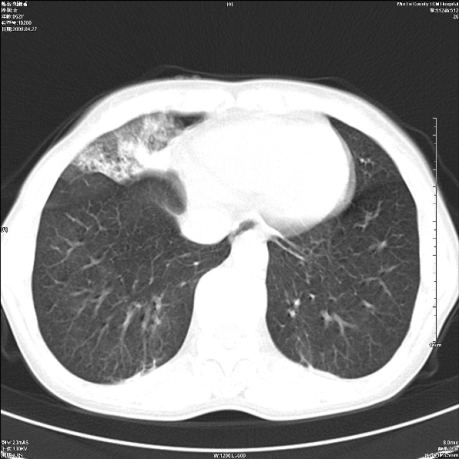

标题: CT19625:女52间断性喀血 [打印本页]

标题: CT19625:女52间断性喀血

考虑右肺中叶感染性病变并右肺中、下叶肺泡积血;建议抗炎、止血治疗后复查。

右肺中叶炎症;右肺中、下叶肺泡积血

右肺中叶支气管扩张并感染或咳血沉积,块右肺中下叶肺泡积血。

右肺中叶慢性炎症伴局部支扩并中下叶肺泡积血。

考虑右肺中叶感染性病变并右肺中、下叶肺泡积血。建议治疗后复查。